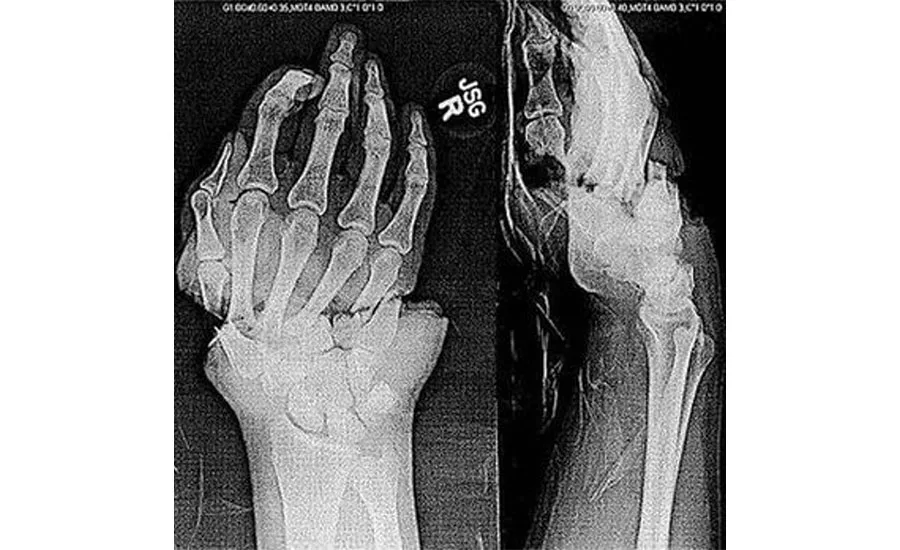

After about a week, the inevitable happened. A hoisted rod had just cleared the string when it unexpectedly dropped and contacted the downhole string, severing the four fingers on his dominate hand. To make matters worse, the fingers — still in a glove — dropped down the inside of the string and would have taken hours of tripping pipe to retrieve. They drove to the hospital without the possibility of reattaching the poor man’s fingers.